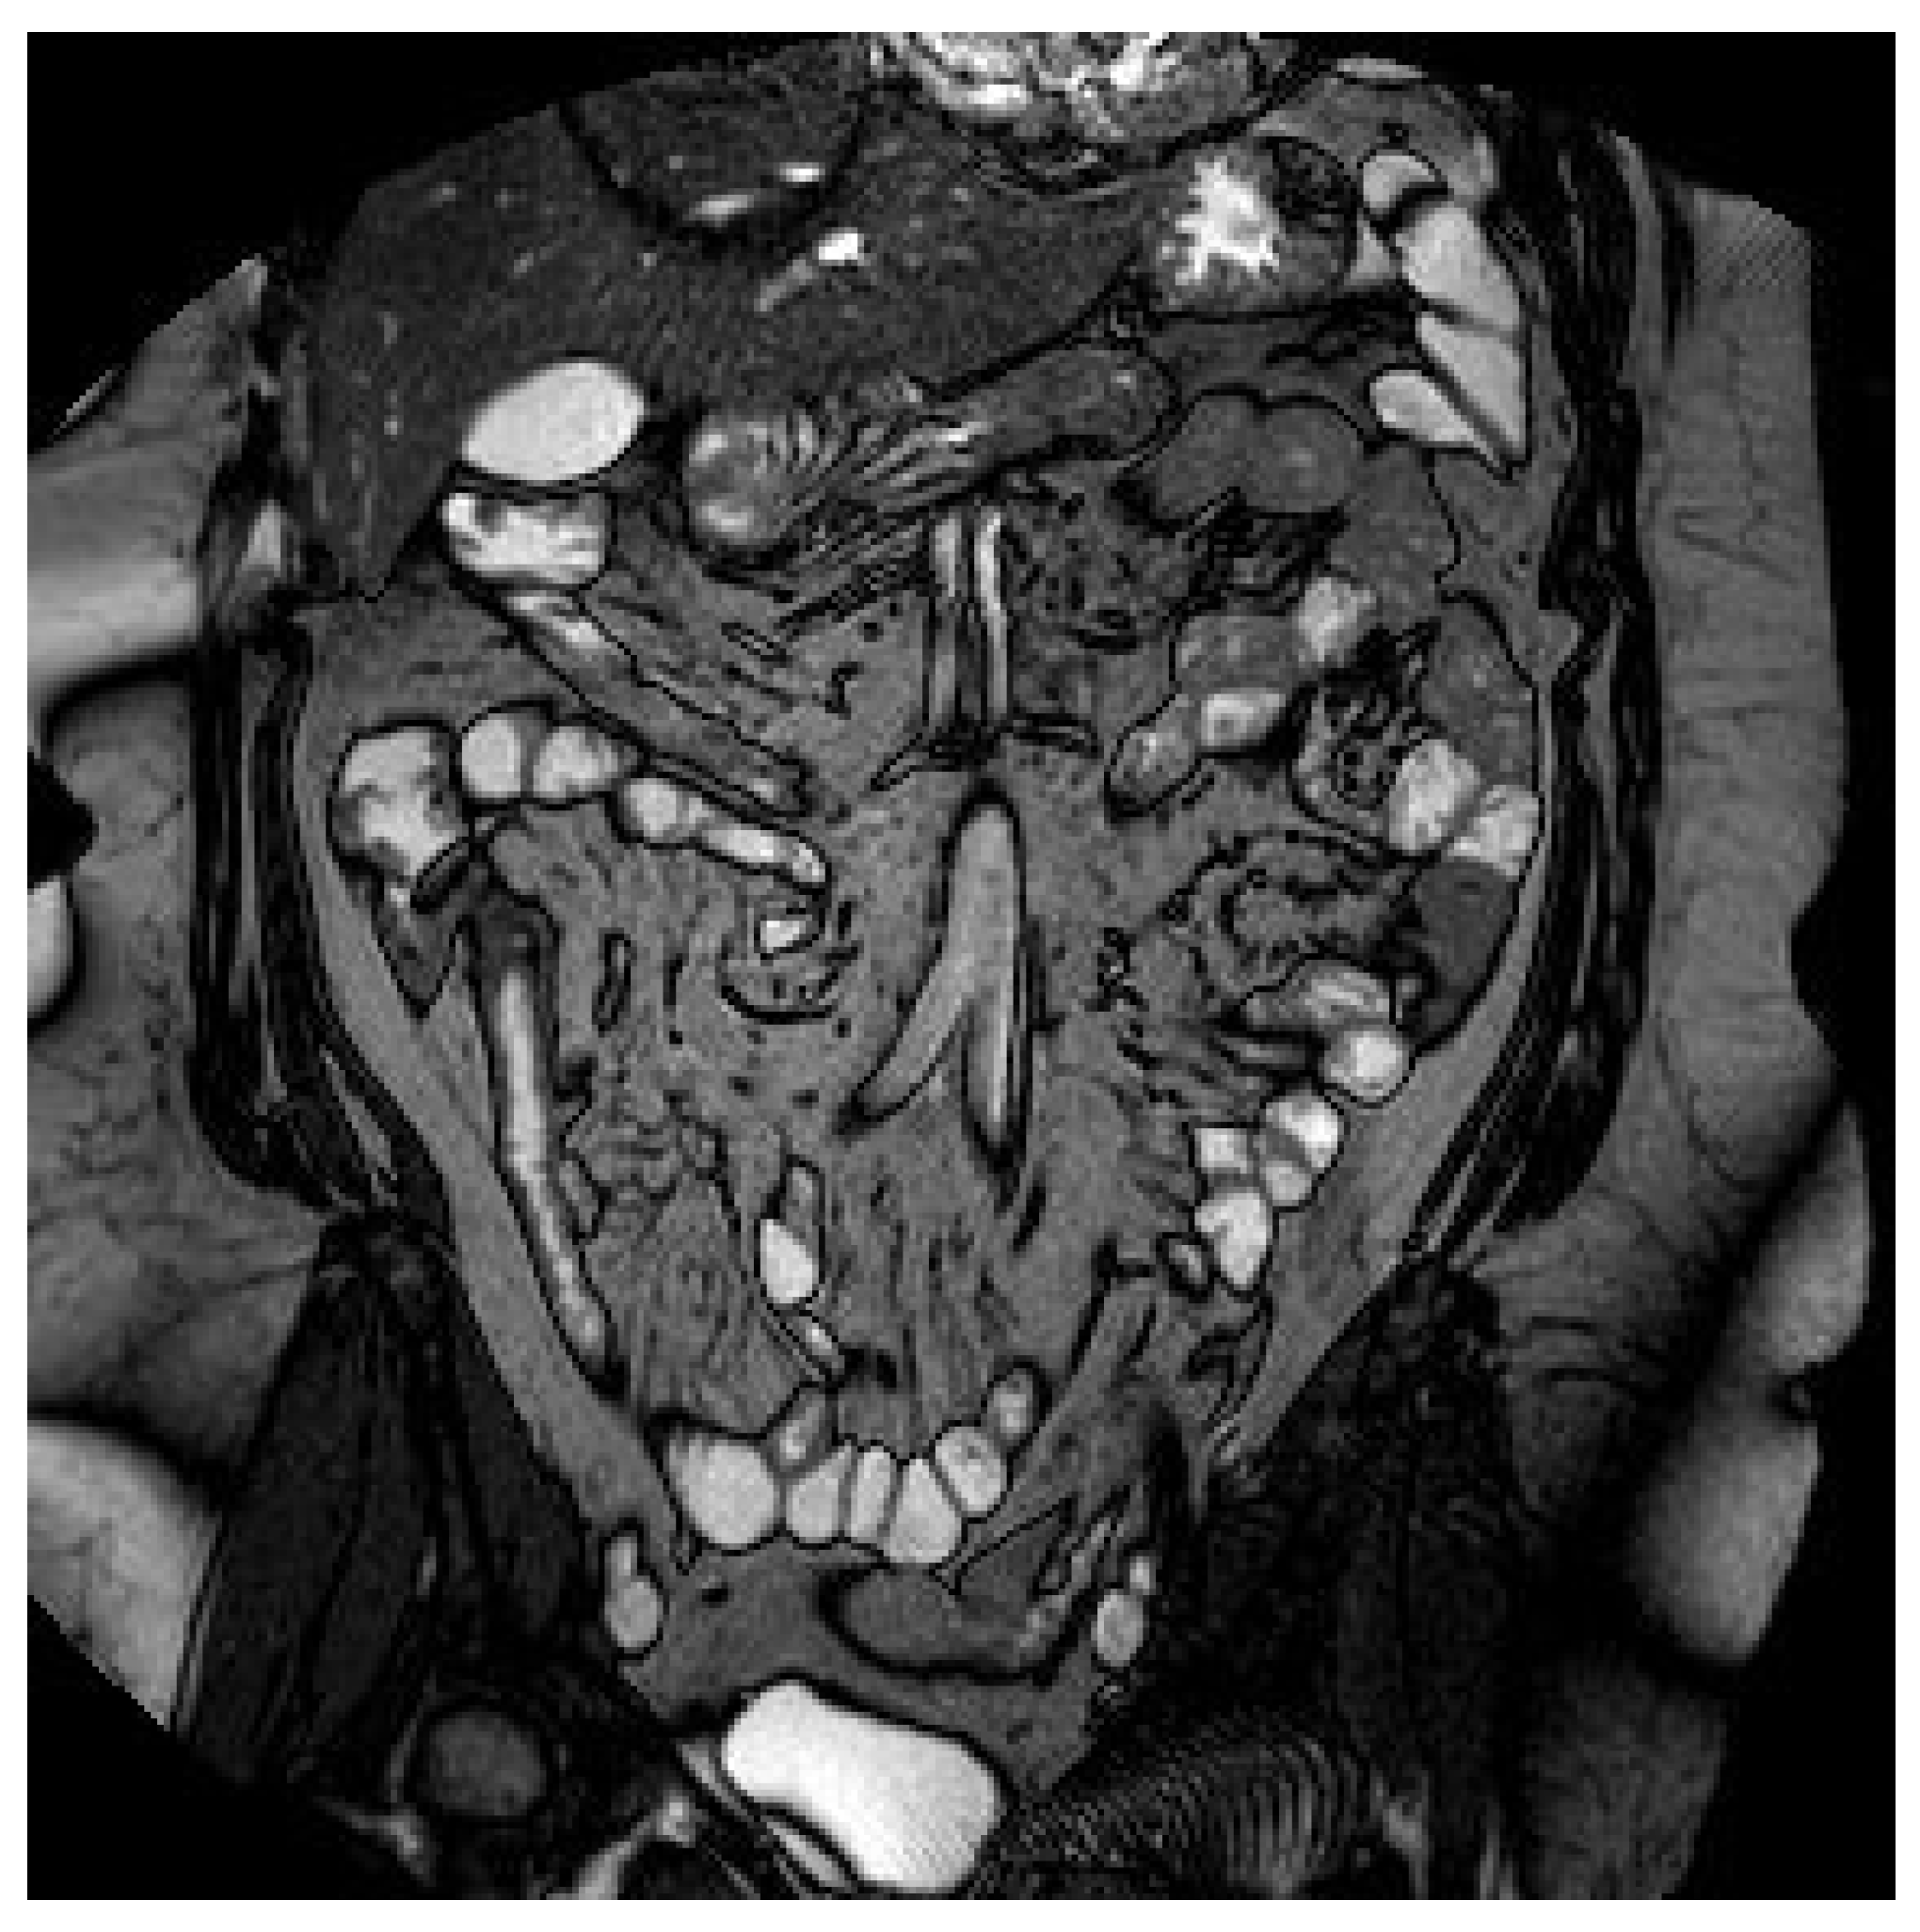

Figure 5.

Magnetic resonance imaging showing a thickening of the distal ileum, extended for 7 cm, with contrast enhancement but without the presence of the fruit pit.

On clinical examination, the abdomen was tender all over the quadrants with absence of peritoneal signs. Laboratory tests showed an increased white blood cell count of 14,000/mm3 and a C-reactive protein of 26.2 mg/dl. Computed tomography scan showed small bowel thickening with a 12 mm intraluminal radiopaque mass (Figure 3). Colonoscopy showed an inflammatory (ulcerated) but serrated stenosis of the terminal ileum with patency of ileocecal valve, suspicious for ileal CD (Figure 4). Magnetic resonance imaging showed thickening of the distal ileum, 7 cm in length, without the presence of the fruit pit, that had been physiologically expelled from the colon (Figure 5). Due to the nature of the stenosis, which was inflammatory, a “wait and see approach” was chosen. After a brief course of systemic prednisone, which failed to obtain any clinical benefit, ileocecal resectionwas performed with resolution of all symptoms.